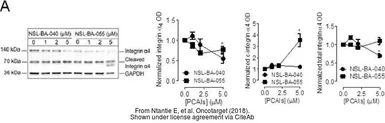

The data was published in the journal Oncotarget in 2018. PMID: 29899821